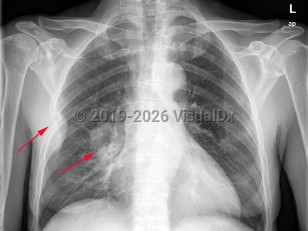

Pneumothorax

Spontaneous pneumothoraxSpontaneous pneumothorax

Tension pneumothorax